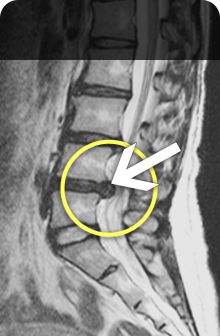

척추와 뼈 사이에 위치한 이 디스크는 외부로부터의 물리적 충격을 완화하고 단단한 뼈가 직접 충돌할 때 문제가 발생하지 않도록 하는 탄성이 높은 구조입니다. 외부의 영향이나 잘못된 위치로 인해 디스크가 꺼지면 염증이 발생하고 신경이 눌려 요통과 요통이 발생합니다. 기술적으로는 요추 디스크 분리라고 하며 일반적으로 요추 디스크 고장이라고 합니다.

허리디스크 진단법

평평한 곳에 누워서 다리를 올리세요. 다리를 제대로 들 수도, 무릎을 땅에 대고 다리를 벌릴 수도, 뒷바퀴가 생기도록 다리를 40~50도 올릴 수도 없습니다.